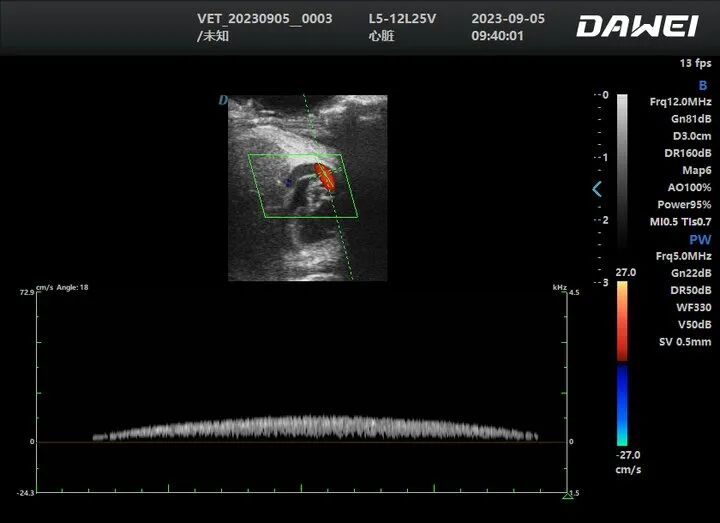

4. Crayfish Ultrasound Case

Objective

- Monitor crayfish cardiac activity and heart rate changes to assess how water temperature, water quality, and other environmental factors affect growth.

System

- Dawei P5-VET Portable Veterinary Color Doppler Ultrasound

How it’s used

- Pond/lab scanning enables real-time heart rate trend recording, then results are compared across different environmental conditions.

Value

- Turns physiological signals into actionable data, helping research teams and farms move from experience-based decisions to data-driven management.